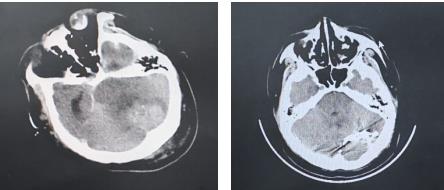

纪文军主任团队制定好手术方案后,快速完善术前准备,争分夺秒,完成术前相关检查,并将常师傅送入介入手术室。在神经外科二病区纪文军主任医师、李涛副主任医师、张伟副主任医师、赵乐副主任医师及麻醉手术科工作人员的紧密协作下,历经约2小时手术,确认病因为后颅窝硬脑膜动静脉瘘合并巨大的静脉瘤破裂出血。术中,团队逐一对硬脑膜动静脉瘘多支供血动脉进行栓塞,术后脑血管造影显示硬脑膜动静脉瘘近全栓塞,巨大静脉瘤不显影。

左图:术前头颅CT 右图:术后头颅CT